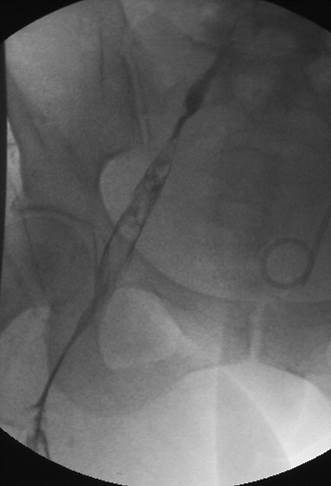

Venograma en posición de decúbito prono de la rama ilíaca izquierda que indica una estenosis causada por el tumor que comprime la uretra y la vena ilíaca externa izquierda.